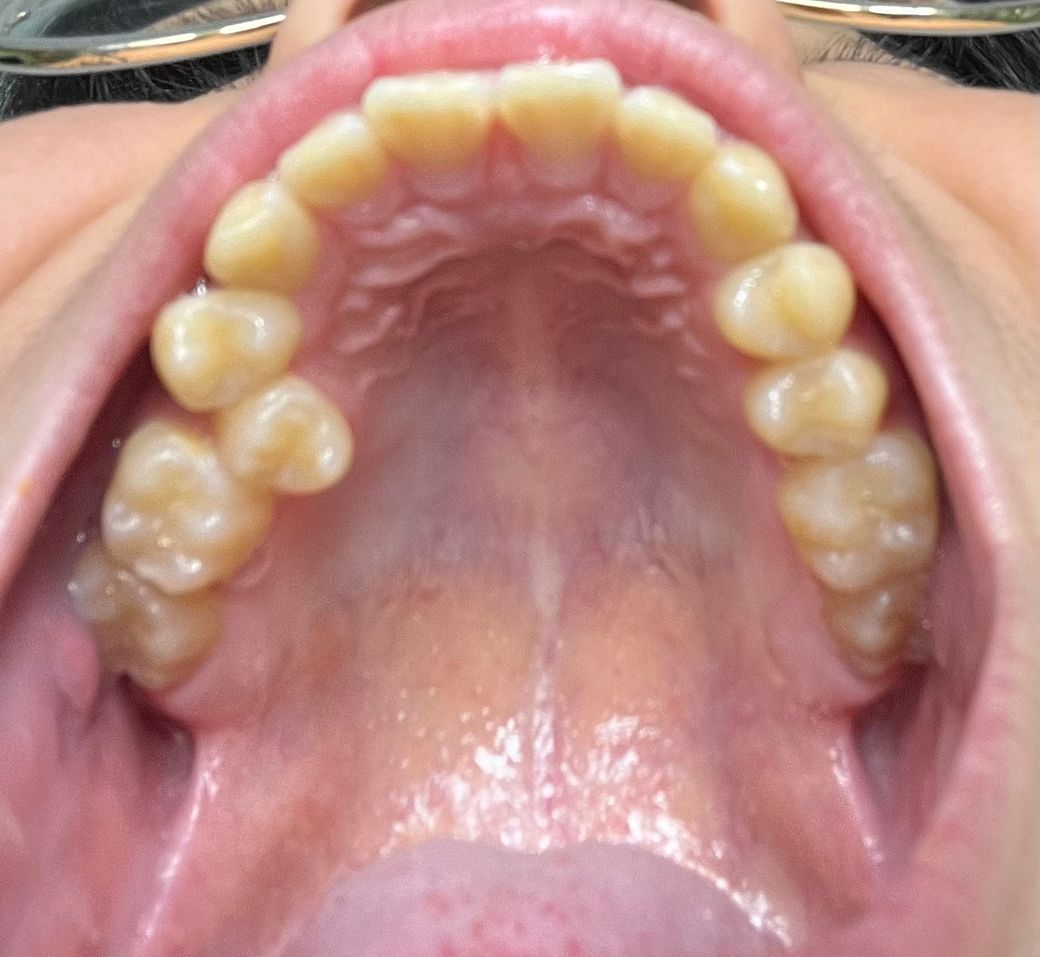

부분교정하고싶은데 이 치아 배열로 가능할까요?

덧니가 나서 가능한한 안보이게 부분교정으로 하고싶습니다.

교정하게 된다면 부분교정으로 가능할까요?

• 1번 째 사진

부분교정 가능여부는 위, 아래 어금니의 맞물림도 확인해봐야 합니다. 이 사진만으론 판단이 쉽지 않습니다. 일단 배열공간이 부족하면 지금 뒤틀려있는 작은 어금니는 발치하고 발치교정가능성이 있습니다.